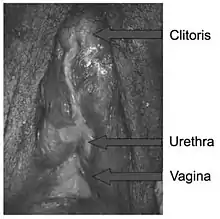

Predominantly male phenotypes vary in the degree of genital undermasculinization to include micropenis, chordee, bifid scrotum, and / or pseudovaginal perineoscrotal hypospadias.[1][18][30] Impotence may be fairly common, depending on phenotypic features; in one study of 15 males with PAIS, 80% of those interviewed indicated that they had some degree of impotence.[31] Anejaculation appears to occur somewhat independently of impotence; some men are still able to ejaculate despite impotence, and others without erectile difficulties cannot.[23][32][33][34] Predominantly female phenotypes include a variable degree of labial fusion and clitoromegaly.[3] Ambiguous phenotypic states include a phallic structure that is intermediate between a clitoris and a penis, and a single perineal orifice that connects to both the urethra and the vagina (i.e. urogenital sinus).[3] At birth, it may not be possible to immediately differentiate the external genitalia of individuals with PAIS as being either male or female,[1][35] although the majority of individuals with PAIS are raised male.[1]

Grade 5, the form of PAIS with the greatest degree of androgen insensitivity, presents with a mostly female phenotype, including separate urethral and vaginal orifices, but also shows signs of slight masculinization including mild clitoromegaly and / or partial labial fusion.[1][3]

If feminizing genitoplasty is performed in infancy, the result will need to be refined at puberty through additional surgery.[78] Procedures include clitoral reduction / recession, labiaplasty, repair of the common urogenital sinus, vaginoplasty, and vaginal dilation through non-surgical pressure methods.[29][47][57][78] Clitoral reduction / recession surgery carries with it the risk of necrosis[78] as well as the risk of impairing the sexual function of the genitalia,[57] and thus should not be performed for less severe clitoromegaly.[29] Clitoral surgery should be focused on function rather than appearance, with care being taken to spare the erectile function and innervation of the clitoris.[29] If PAIS presents with a common urogenital sinus, the American Academy of Pediatrics currently recommends that surgery to separate the urethra from the vagina be performed at an early age.[79] As is the case for CAIS, vaginal dilation using pressure dilation methods should be attempted before the surgical creation of a neovagina is considered, and neither should be performed before puberty.[29][47] Complications of feminizing genitoplasty can include vaginal stenosis, meatal stenosis, vaginourethral fistula, female hypospadias, urinary tract injuries, and recurrent clitoromegaly.[47][77] Successful feminizing genitoplasty performed on individuals with grade 3 PAIS often requires multiple surgeries, although more surgeries are typically required for successful masculinizing genitoplasty in this population.[24]